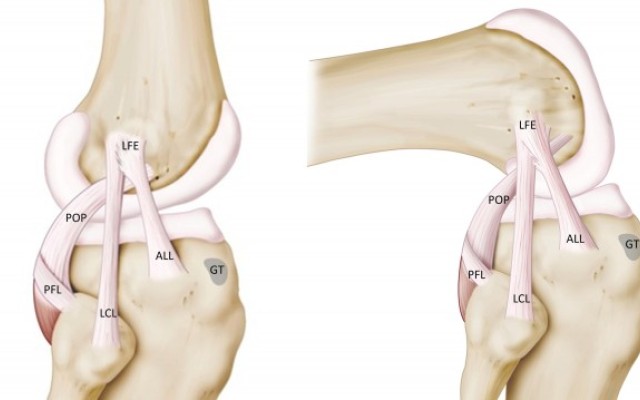

Antero-Lateral Ligament Augmentation to ACL reconstruction.

The anterolateral ligament(ALL) is a ligament on the lateral aspect of the human knee, anterior to the fibular collateral ligament. Perhaps the earliest account of the ALL was written by French surgeon Paul Segond in 1879, in which he described a ligamentous structure between the lateral femur and tibia.

The ALL, which has been suggested to occur in at 33-97% of...